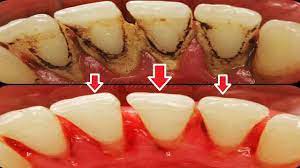

দন্তরোগ

Read moreহার্টবিট ডেস্ক ডেন্টাল ক্যারিজ অর্থ দাঁতের মধ্যে গর্ত হয়ে যাওয়া বা দাঁত ক্ষয়ে যাওয়া। আর এই ডেন্টাল ক্যারিজ সময়মতো চিকিৎসা...

Read moreঅধ্যাপক ডা: অরূপ রতন চৌধুরী আমাদের দেশে দাঁতের ক্ষয় বা গর্ত হওয়াকে অনেকেই দাঁতের পোকা বলে। কিন্তু বিজ্ঞানীরা শত চেষ্টায়ও...